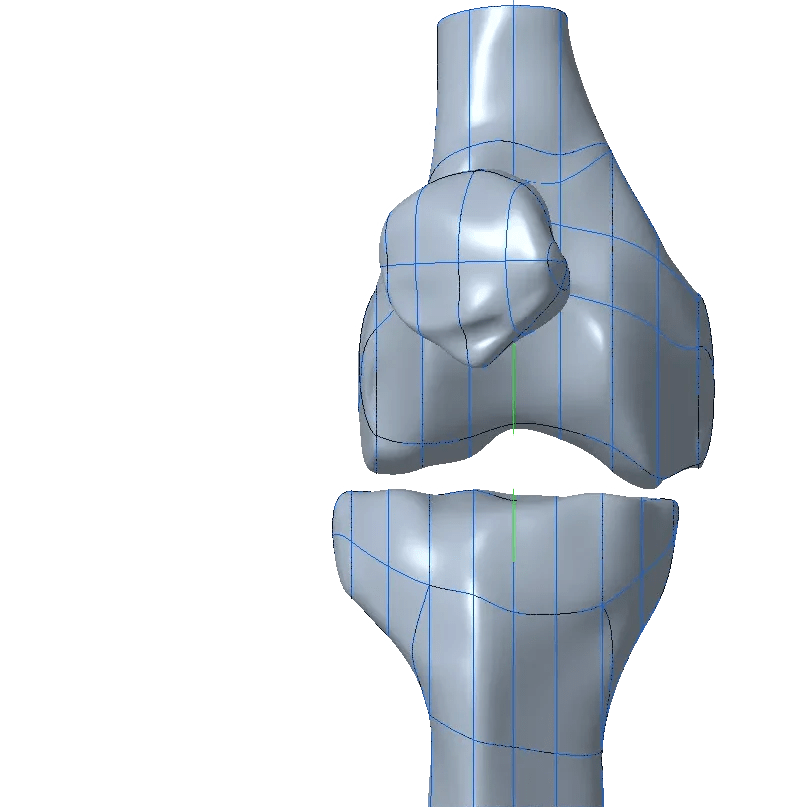

We used parametric modeling to build a surfacee model to the bones. Steb by step process below.

Using the voxel models and the MRI scans and a bonus surface scan we fit all together and analysed the patient which construction would be the best for them.

solid model vs segmented model

skin shell

verify shape

To give a more detailoed picture we built up a motion skeleton to move the bones and used the biomechanics of the knee to place the hinge and to create the design.